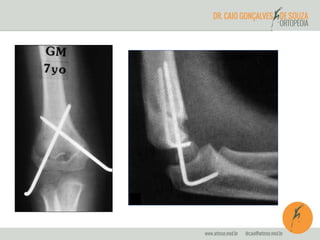

TRATAMENTO

•Fratura sem desvio (TIPO I) – imobilização com aparelho gessado

•Fratura em galho-verde (TIPO II) – redução sob anestesia e

imobilização com aparelho gessado

•Fratura com desvio total (TIPO III) – redução incruenta e fixação

percutânea com fios de Kirschner